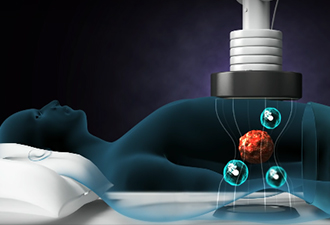

암 환우·가족에 영적 위로 및 최신치료 정보 제공CCS부천소사구기독교총연합회·아디포랩스, 희망 나눔 컨퍼런스 개최국내 암 치료 석학 대거 참석, 최신 온열 암 치료 사례·임상 결과 공유【후생신보】 암 환우와 가족들에게 영적인 위로와 실질적인 치료 정보를 제공하는 희망 나눔 컨퍼런스가 열렸다. CCS부천소사구기독교총연합회(회장 최..

아디포랩스, 몽골 진출 교두보 마련…글로벌 시장 확대 ‘가속페달’몽골 Med Innovation Bridge LLC와 고주파 온열암치료기 ‘리미션 1°C’ 독점 유통 MOU한성호 대표 “현지 파트너와 긴밀한 협력 통해 글로벌 의료기기 시장확대 가속화할 것”【후생신보】 고주파온열암치료기 ‘리미션1℃’로 전 세계 암 환자들에게 희망을 주고 ..